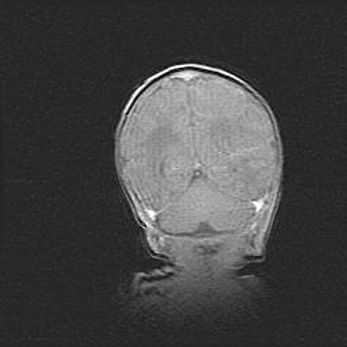

Церебральная ишемия II.

Возраст: 5 дней

Вес: 3400 г

Пол: женский

Окружность головы: 35 см

Срок гестации: 39 недель

Церебральная ишемия – это заболевание, характеризующееся недостаточностью (гипоксией) либо полным прекращением (аноксией) снабжения мозга кислородом по причине закупорки одного или нескольких сосудов. Это приводит к  что метаболическим расстройствам различной степени тяжести в тканях головного мозга, развитию коагуляционных некрозов и гибели нейронов.